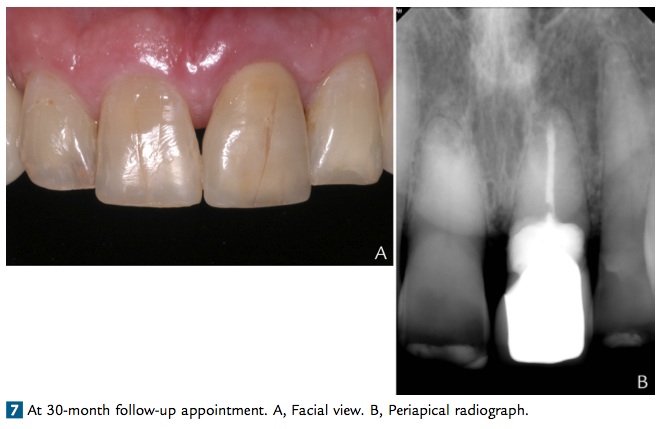

這篇文章是一個case report, 一位78歲的老先生因為在25年前有撞到左上正中門牙, 造成慢性的吸收. 可能是考量年紀的問題所以沒有去植牙(作者群在文章中有提到, 怕牙肉向下萎縮…) 所以他們先做endo, 然後flap op下去補GI modified resin cement, 再做crown. 在六個月後照CT發現facial bone有缺損所以再補一次bone. 後來觀察到30個月結果都是不錯的…